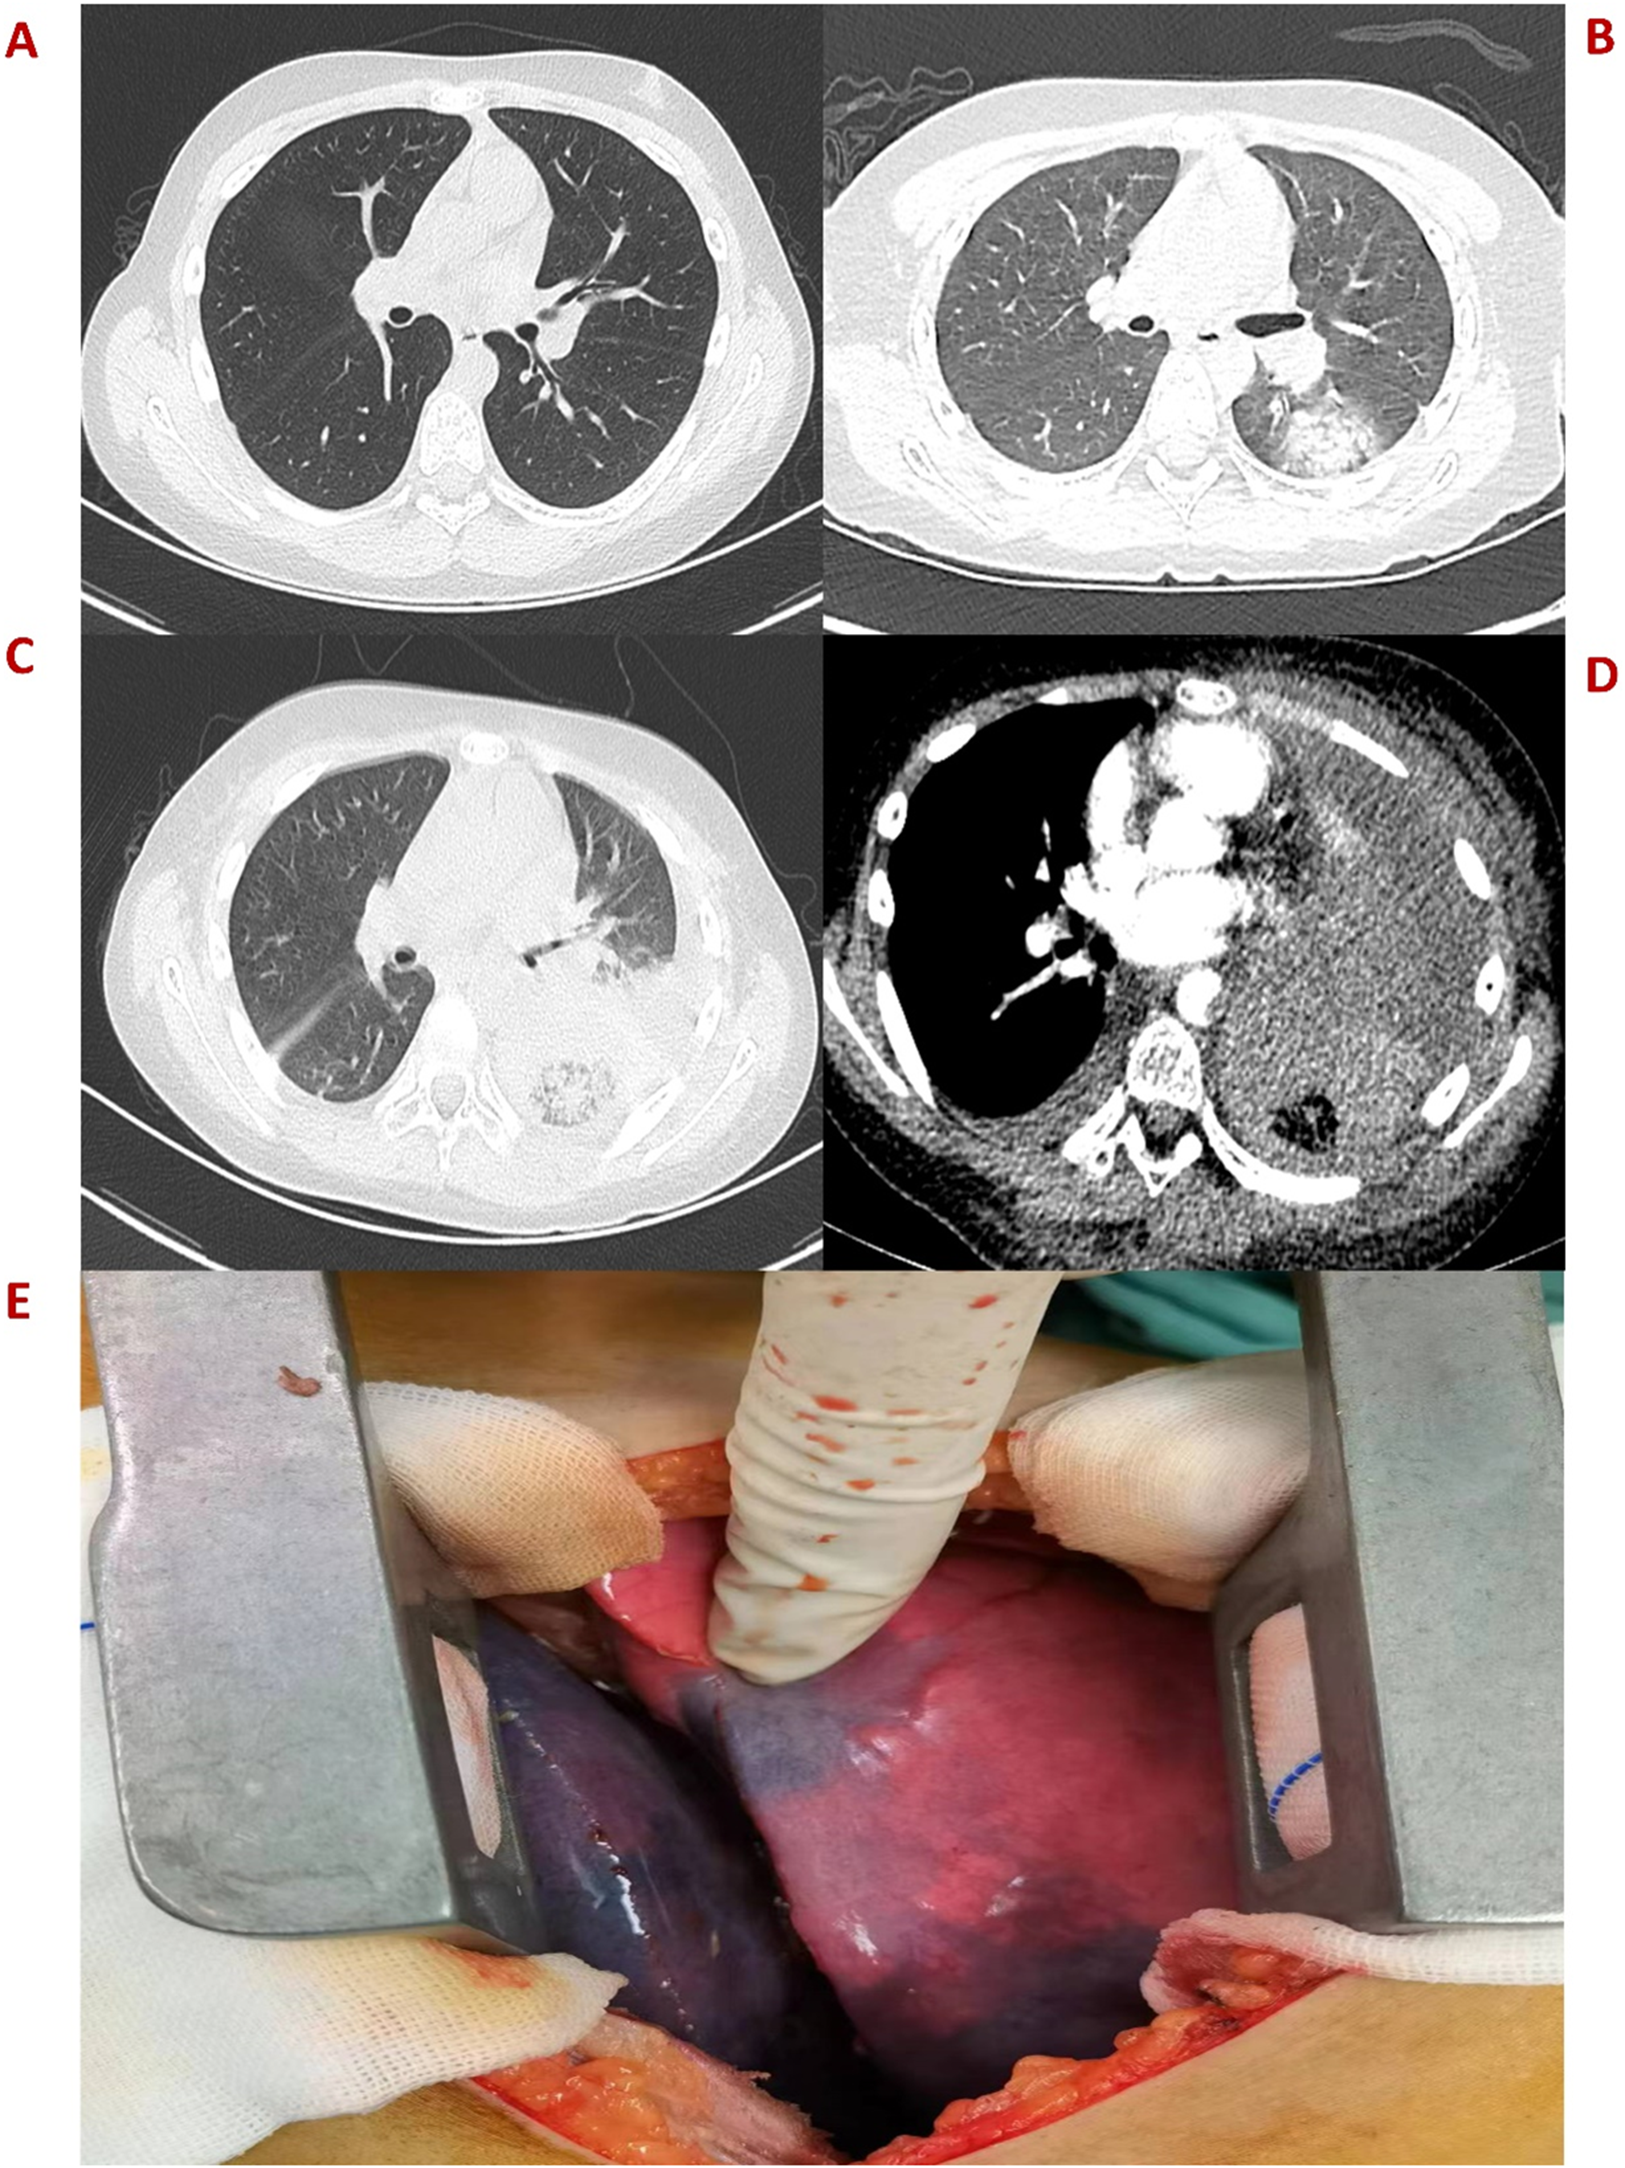

An 11-year-old boy was admitted to the hospital on October 11, 2022, due to hemorrhagic spots on the skin that had lasted for 1 week, and gingival bleeding that had been present for 1 day. He came from a well-off family and there was no previous medical, family, and psychosocial history. Initial laboratory analysis revealed the following data: white blood cell count 0.97 × 109/L, absolute neutrophil count 0.06 × 109/L, hemoglobin count 99 g/L, reticulocyte count 0.01 × 109/L, platelet count 1 × 109/L. The blood test showed a simultaneous decrease in the ternary system. The nucleated cell count in bone marrow was severely reduced, particularly because of leukocytes (92.5%) and not megakaryocytes. The bone marrow pathological analysis revealed a notable reduction of hematopoietic cells and an increase in non-hematopoietic cells such as fat cells. Moreover, his full exon sequencing, chromosomal aberration, comet, and gene mutation assays were negative. AA is a hematopoietic stem cell disorder featuring reduced bone marrow cellularity and decreased hematopoiesis. The diagnosis of aplastic anemia requires the presence of all four of these criteria: (1) Peripheral blood cytopenia, defined as two or more of the following: hemoglobin <100 g/L, absolute neutrophil count < 1.5 × 109/L, platelet count < 50 × 109/L. (2) Hypocellular bone marrow, defined as the presence of a bone marrow biopsy with cellularity <25% of normal for the patient's age. (3) Absence of dysplasia, infiltration, or fibrosis in the bone marrow. (4) Exclusion of other causes of pancytopenia, such as paroxysmal nocturnal hemoglobinuria, myelodysplastic syndrome, or other hematological malignancies. The modified Camitta criteria classified AA into three categories on the basis of bone marrow cellularity, an absolute neutrophil count, platelet count, and reticulocyte count. The criteria of SAA included marrow hypocellularity < 25% and at least two of the following: absolute neutrophil count < 0.5 × 109/L, platelet count < 20 × 109/L, and reticulocyte count < 20 × 109/L. Additionally, in VSAA, there is extreme neutropenia of < 0.2 × 109/L (1, 7). Based on Camitta criteria, the child was diagnosed with VSAA. Although there are many known etiologies; however, unlike the majority of the cases, the etiology of VSAA was difficult to determine in this child (1, 2), and he was managed as a case of idiopathic acquired VSAA. To treat the primary disease, he was given cyclosporine on day 8 until a rash appeared on day 10. After the admission, the child developed a fever with no obvious swelling of the liver, spleen, or lymph nodes. Laboratory analysis revealed the following data: white blood cell count 0.58 × 109/L, absolute neutrophil count 0.08 × 109/L, hemoglobin count 83 g/L, reticulocyte count 0.01 × 109/L, platelet count 1 × 109/L, C-reactive protein (CRP) count 52 mg/L, and ferritin count 450 ng/dl. Furthermore, 1, 3-b-D glucan, serum galactomannan antigen, and blood culture analyses indicated negative results on multiple occasions. All pathogen tests including epstein-barr virus virus, cytomegalo virus, hepatitis virus, etc.,are negative, and no obvious infectious lesions are found in the CT scans of the head and chest (Figure 1A) and in the abdominal ultrasound. On the day of admission with neutropenia and fever, meropenem was added immediately for anti-infective treatment. Despite aggressive anti-infection therapy (i.e., meropenem, teicoplanin, linezolid, levofloxacin, and imipenem/cystatin) (Figure 2) for nearly two weeks, there was persistent fever, intermittent hemoptysis, and chest wall pain. These persistent clinical symptoms and rapid progression of pulmonary infection as evident in the pulmonary CT (indicated an area of ground-glass opacity surrounded by consolidation on day 12 (Figure 1B), led to the diagnosis of a mixed bacterial and fungal infection. Antibiotics were changed and antifungal drug (caspofungin) was added as the symptoms of infection were not alleviated. To treat severe granulocytopenia, infections, and inflammatory response, on day 12 the granulocyte colony-stimulating factor (G-CSF), gammaglobulin, and methylprednisolone were administered. On the day 16th, mNGS indicated that he was positive for Cunninghamella bertholletiae. As mNGS suggested a single infection of Cunninghamella bertholletiae, amphotericin B was added for antifungal treatment immediately. In the chest CT on day 22, the left lung revealed a consolidation enlargement with central ground-glass shadows, recognized as the reverse halo sign (RHS) (Figure 1C), indicative of a characteristic feature of PM (6). Although the antifungal therapy (i.e., amphotericin B liposome, caspofungin, and isavuconazole) (Figure 2) was started, there was still a persistent fever, severe agranulocytosis, and uncontrolled pulmonary infection. Notably, the lung CT suggested the presence of a left lower lobe infarction on day 30 (Figure 1D). Therefore, as a timely intervention, emergency surgery was performed, which caused a left lower lobe infarction during the procedure (Figure 1E), confirming the initial suspicion. After collaboration with the radiology department, a pulmonary infarction was identified. Subsequently, a timely surgical intervention involving a left lower lobectomy and the removal of pulmonary artery thrombosis was performed, which effectively preserved the crucial time for the patient's survival. During the surgery, routine histopathological examination of the lung tissue was performed, but the result was negative. Despite the successful operation and the administration of amphotericin B into the chest cavity via the left thoracic drainage tube, the patient continued to suffer from a severe infection. This persistent infection stimulated an increased inflammatory response, as evident by progressively elevated levels of CRP (>200 mg/L) and ferritin (>10,000 ng/dl). Although the fungal culture test was negative, mNGS detection performed on pleural effusion revealed the presence of Cunninghamella bertholletiae on day 32, indicating a severe infection and elevated inflammatory response. Multiple postoperative chest x-ray examinations revealed left pleural effusion and a progressive worsening of pulmonary infection. Based on adequate anti-infective treatment, methylprednisolone, etoposide, ruxolitinib, and plasma exchange were administered to control inflammatory response (Figure 2). On day 42, the child went into convulsions, indicating a deteriorating condition. Since initially, the cranial CT appeared normal, intracranial infection was diagnosed. Subsequent lumbar puncture revealed clear yellow cerebrospinal fluid (CSF) with significantly low glucose, elevated protein, and decreased chloride levels, confirming an intracranial infection. Consequently, intensified anti-infective therapy was initiated. Despite the administration of intensive therapies, he died of severe septic shock and disseminated intravascular coagulation dysfunction (DIC) on day 45. The Ethics Committee of the Union Hospital of Tongji Medical College, Huazhong University of Science and Technology approved this study.

Figure 1

(A) Plain CT scan image of the left lung on day 2. (B) An emergency CT scan image obtained after 12 days indicates patchy ground-glass shadows in the dorsal segment of the left lower lobe. (C) An enhanced CT image obtained after 22 days shows a reverse halo sign in the left lung. (D) Enhanced CT image obtained on day 30 presents the left lung infarction. (E) Surgical photos of lesions showing the left lower lobe infarction.